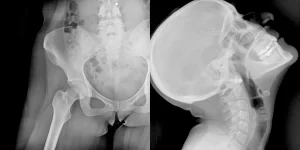

Los rayos X dinámicos son un tipo de radiografía que captura imágenes en movimiento de las articulaciones y la columna vertebral. A diferencia de las radiografías convencionales, que muestran imágenes estáticas, los rayos X dinámicos permiten a los médicos observar cómo se comportan las articulaciones y la columna durante el movimiento.

Durante un RX dinámico, el paciente se mueve de acuerdo a las indicaciones del técnico mientras se toman las imágenes. Estas imágenes en movimiento ayudan a los médicos a evaluar la funcionalidad de las articulaciones y la columna vertebral. Los rayos X dinámicos pueden realizarse en diversas partes del cuerpo, incluyendo la columna, el hombro, la muñeca, la rodilla y el tobillo.